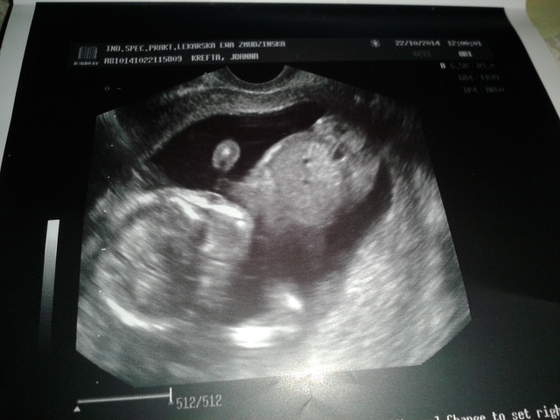

A to moje Motylki :-) przepraszam za kiepską jakość:zawstydzona/y:

14tc razem.jpg14tc ser1.jpg14tc ser2.jpg